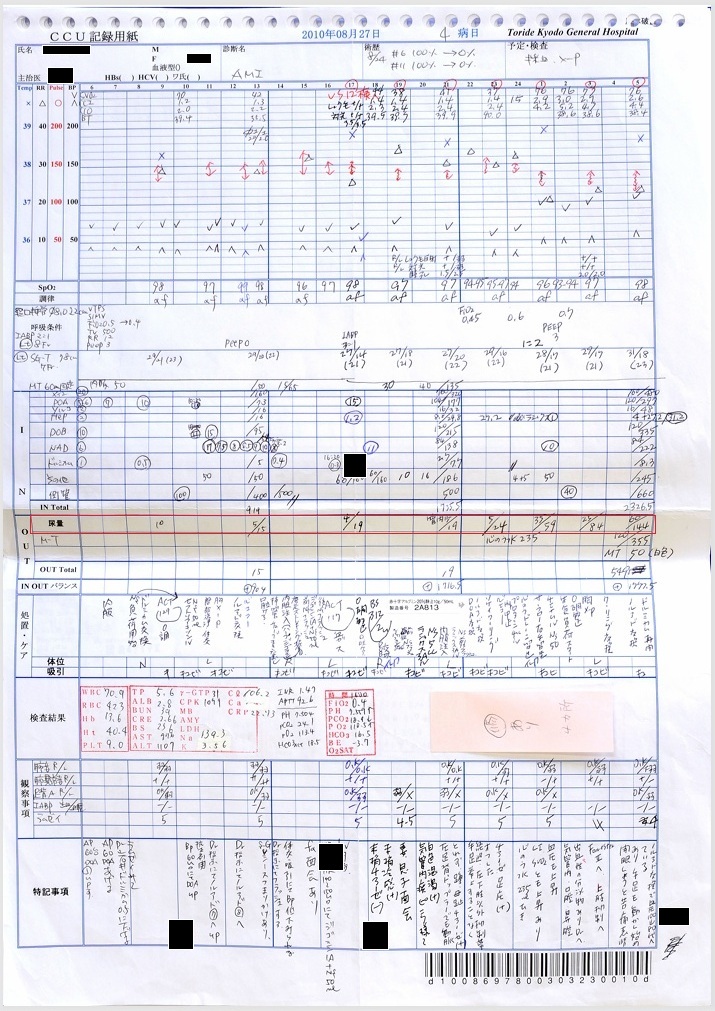

- 8月25~28日:ショックに伴う乏尿・無尿・危篤状態

8月25日:尿量779ml/日、8月26日21:30~8月27日5:30:尿量28 ml, 8月27日5:30~13:30:尿量15 ml, 13:30~21:30:尿量4 ml, 21:30~8月28日5:30:尿量144 ml(ショックに伴い無尿、ショック解除に伴い尿量増加。)

証拠:CCU看護記録(尿量)

- 8月27日:APTT 92秒でヘパリン増量(死期を故意に早めようとした疑い)

胸腔、心嚢内への出血によるショックの進行中、8月27日の血液検査でAPTT 92秒とパニック値にもかかわらず、ヘパリンを15000単位から20000単位に増量。故意に死期を早めようとした疑い。

証拠:血液検査・注射処方箋の抜粋(赤枠部分)

- 8月27日:医師・看護師、心嚢水増量、危険な状態を認識

当日のカルテには「心嚢水増量」、「危険な状態」との記載あり。

証拠:カルテ記載

8月27日の午後3時の時点で、血圧60/40 mmHg, 心拍数150~160/min、8時間尿量4mlと、いつ心肺停止してもおかしくない状態であった。 しかし医師は父がショックに陥った原因を「元々の心筋梗塞が重症のため」と偽り、 医療事故とそれに起因する緊張性血胸・心タンポナーデ、出血性ショックを隠蔽した。 またヘパリン15000単位/日が投与されていたが、この日の血液検査でAPTT 92秒とヘパリン投与量が過剰であったにもかかわらず、ヘパリンが20000単位/日に増量されており、故意に死期を早めようとした疑いがある。